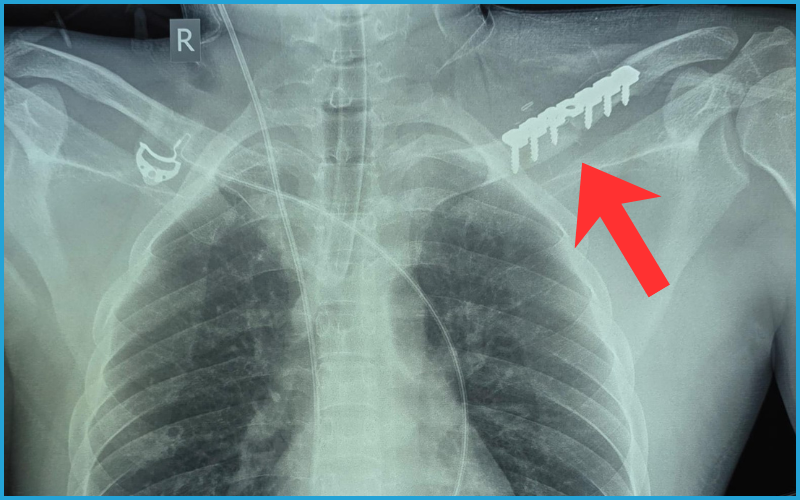

क्षतिग्रस्त धमनी को जोड़ने के लिए 7×30 मिमी का डेक्रॉन ग्राफ्ट लगाया गया। यह एक विशेष प्रकार की कृत्रिम नस होती है, जिससे रक्त प्रवाह को पुनः स्थापित किया जाता है। करीब चार घंटे तक चले ऑपरेशन के दौरान मरीज को लगभग 5 यूनिट रक्त चढ़ाया गया। सर्जरी की सबसे बड़ी चुनौती ब्रैकियल प्लेक्सस तंत्रिका तंत्र को सुरक्षित रखना थी, क्योंकि इसमें क्षति होने पर हाथ में स्थायी लकवे का खतरा रहता है। डॉक्टरों ने अत्यंत सावधानीपूर्वक यह प्रक्रिया पूरी की।ऑपरेशन के अंतिम चरण में कॉलर बोन को पुनः प्लेट लगाकर जोड़ा दिया गया, जिससे हाथ की संरचना और मजबूती बनी रहे।